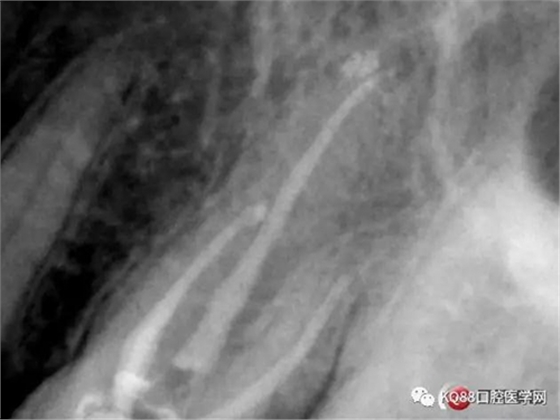

當(dāng)我第一次完成操作后,再次拍了一個(gè)插針片,發(fā)現(xiàn),距離根尖孔有1.5mm,書上說(shuō)的是2mm安全區(qū),可能如果隨意點(diǎn),就直接充填了,我想說(shuō)明的是,我們做根管,千萬(wàn)不要馬虎,不要湊合,一定嚴(yán)謹(jǐn)?shù)膽B(tài)度,于是我重新再回到C銼,再開始耐心的預(yù)備,完成之后,再拍攝了插針片。

此次明顯可以看見(jiàn)根尖分開了兩個(gè)根尖孔,根管治療永遠(yuǎn)就只是那一點(diǎn),如果都只是隨便做一下,我相信,沒(méi)有復(fù)雜的牙齒,根管治療都會(huì)很簡(jiǎn)單,態(tài)度決定一切,我不敢說(shuō)我做的會(huì)很好,但是我會(huì)靜下心來(lái),慢慢操作,這樣才能做得對(duì)的起自己和患者。于是根充完成,再次拍攝。